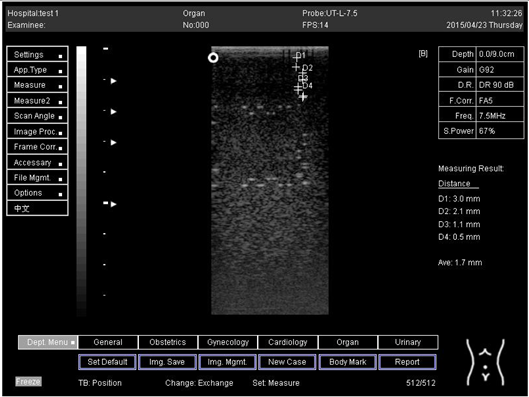

6.0 Axial resolution

Biomimetics 07 00130 i013

D1 = 3.0

D2 = 2.0

D3 = 1.0

D4 = 0.6

6.0Lateral resolution

Biomimetics 07 00130 i014